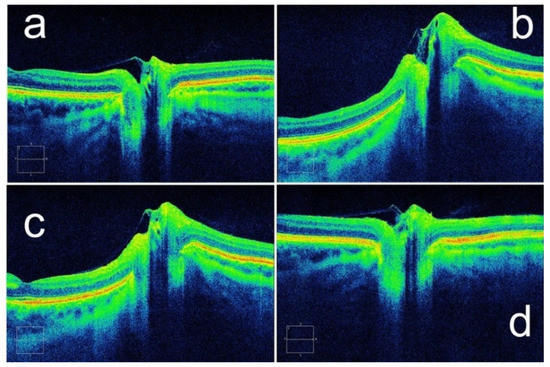

- Kupersmith, M.J.; Sibony, P.; Mandel, G.; Durbin, M.; Kardon, R.H. Optical coherence tomography of the swollen optic nerve head: Deformation of the peripapillary retinal pigment epithelium layer in papilledema. Investig. Ophthalmol. Vis. Sci. 2011, 52, 6558–6564. [Google Scholar] [CrossRef] [Green Version]

- Sibony, P.; Kupersmith, M.J.; Honkanen, R.; Rohlf, F.J.; Torab-Parhiz, A. Effects of lowering cerebrospinal fluid pressure on the shape of the peripapillary retina in intracranial hypertension. Investig. Ophthalmol. Vis. Sci. 2014, 55, 8223–8231. [Google Scholar] [CrossRef] [Green Version]

- Tun, T.A.; Wang, X.; Baskaran, M.; Nongpiur, M.E.; Tham, Y.C.; Perera, S.A.; Strouthidis, N.G.; Aung, T.; Cheng, C.Y.; Girard, M.J.A. Variation of Peripapillary Scleral Shape with Age. Investig. Ophthalmol. Vis. Sci. 2019, 60, 3275–3282. [Google Scholar] [CrossRef] [PubMed] [Green Version]

- Wang, X.; Tun, T.A.; Nongpiur, M.E.; Htoon, H.M.; Tham, Y.C.; Strouthidis, N.G.; Aung, T.; Cheng, C.Y.; Girard, M.J. Peripapillary sclera exhibits a v-shaped configuration that is more pronounced in glaucoma eyes. Br. J. Ophthalmol. 2022, 106, 491–496. [Google Scholar] [CrossRef] [PubMed]

- Jacobsen, H.H.J.K.; Moe, M.C.; Petrovski, G. Non-invasive Estimation of Pulsatile and Static Intracranial Pressure by Optical Coherence Tomography. Transl. Vis. Sci. Technol. 2022, 11, 31. [Google Scholar] [CrossRef]